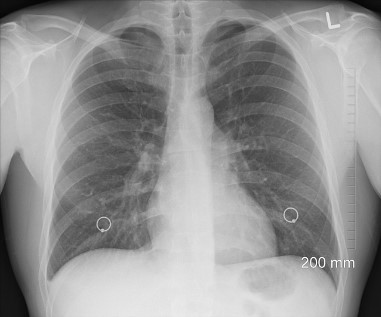

기흉은 흉부 내부의 공기가 비정상적으로 폐 외부로 누출되는 상태를 말합니다. 폐에 구멍이 나면 폐의 압력이 가슴속의 압력과 같아져서 사슴 속의 부피에 따라 폐가 커지거나 작아지지 못하므로 공기가 폐로 나가지 못하게 되어 호흡곤란이 일어납니다.

기흉이 발생하면 폐의 일부 또는 전체가 흉강으로 이동하게 됩니다. 기흉은 폐와 흉강 사이의 압력 차이로 인해 발생할 수 있습니다.